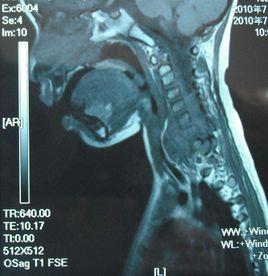

本病常並發其他先天性畸形,以脊椎相應部位的畸形居多,如顱骨凹陷、寰枕畸形、椎體融合、脊椎裂、半椎體、脊膜膨出、脊柱側彎等:另外還伴有消化道、呼吸道畸形,如腸臂異位、食管或氣道憩室、支氣管和縱隔囊腫、縱隔或枕骨鱗部缺損等。此外在高頸段者還可伴發小腦扁桃體下疝畸形,參見本節典型病例。

本病的診斷可根據病人為男性兒童或青少年;以根性疼痛起病,計較快地出現脊髓壓迫症;病程中有間隔數月或數年的反覆發作,如發現有其他先天性畸形,即應考慮有腸源性囊腫,應及時做椎管造影或MRI檢查明確診斷。 在鑑別診斷上需注意與以下椎管內囊性疾病區分: 蛛網膜囊腫 多見於青年人,女性多於男性,好發於胸段脊髓的背側,臨床表現以胸背部疼痛為主,並逐漸出現雙下肢感覺。運動障礙。在坐位或立位時症狀明顯或加重,臥位時症狀緩解。病變部位棘突有壓痛和叩擊痛。腦脊液壓力不高,椎管腔有不全性或完全性梗阻,細胞數正常,蛋白含量輕度增高。脊椎x線平片多無改變,脊髓造影可呈囊狀充盈缺損,俯臥位造影為陰性,仰臥位造影為陽性,仰臥位或立位時才顯示囊腫陰影。MRI檢查顯示脊髓背側梭形囊狀占位,在T1加權像上為一塊狀軟組織強度的信號影.加權像上為高強度信號,增強掃描多無強化。 脊髓蛛網膜炎 起病緩慢,症狀時輕時重.多在外傷或感冒發熱後起病。感覺障礙比較明顯,感覺改變區域的分布常不規律,無明顯的感覺障礙平面。一般運動障礙和括約肌障礙較輕或不明顯。病程多有被動,並有較長的緩解期,呈多灶性體徵。脊髓造影呈散在點狀、片狀或燭淚狀和囊腫充盈缺損。 皮樣囊腫或表皮樣囊腫 多見於小兒,好發於下胸椎以下的圓錐、馬尾部。多位於脊髓外硬骨膜內,常並發脊椎裂。囊腫所在部位有竇道、多毛、血管痣等各種皮膚異常。腦脊液蛋白含量明顯增高。x線檢查可顯示椎管擴大、椎弓根變扁、椎體後緣有向內的壓跡。MRI檢查皮樣囊腫中含有蛋白,故在T1加權像上信號略高於腦脊液,在T2加權像上呈高信號,與腦脊液相似。而表皮樣囊腫在T1與T2加權像上的信號均與腦脊液相似,但囊腫邊界光滑,呈圓形或卵圓形,可見壓迫脊髓和馬尾的表現。